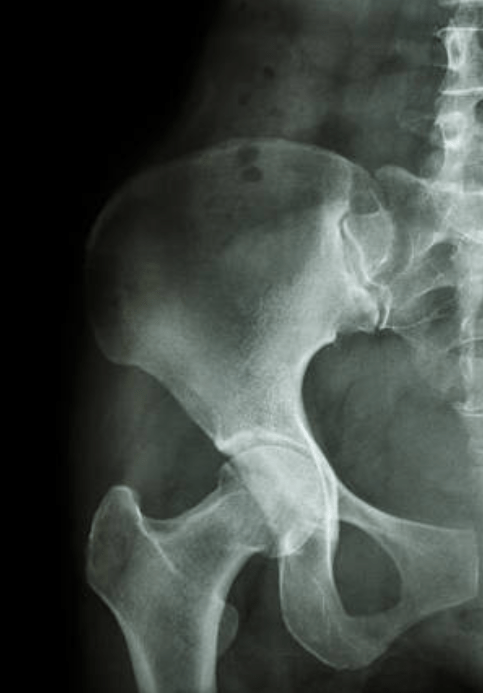

Hanche

La hanche est l’articulation qui relie le bassin au fémur, permettant à la jambe de se déplacer dans toutes les directions tout en supportant le poids du corps.

Elle est constituée de :

• La tête fémorale : la partie supérieure du fémur, qui s’emboîte dans la cavité du bassin appelée cotyle.

• Cartilage et ligaments : assurent la mobilité et la stabilité.

• Muscles autour de la hanche : ils contrôlent la marche, la montée d’escaliers et les mouvements du quotidien.